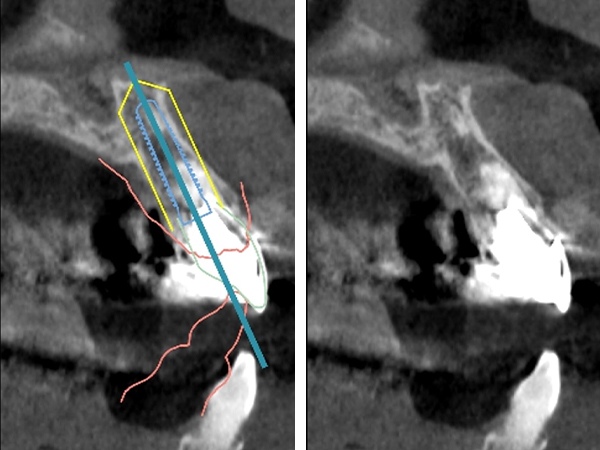

CTによる診査

CTを撮影し、歯根の長さや根尖病変の大きさを精査しました。

CTによるシミュレーション

2|

|1